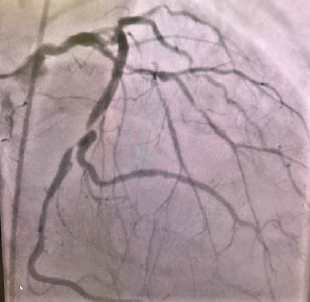

Coronary anatomy revealed a normal left main and an occlusion in the ostial left anterior descending (LAD) at 95%, proximal LAD 70%, mid-LAD 90%, mid left circumflex (LCx) 85%, obtuse marginal (OM)1 70%, OM2 40%, 1st left posterolateral artery 70%, ostial left posterior descending artery 90%, and a right coronary artery (RCA) 100% chronic total occlusion (CTO) (Figures 2-4).

After selective coronary angiography revealed severe triple-vessel coronary artery disease (CAD), it was deemed prudent to obtain a surgical evaluation. Prior to closing the case, an aortogram was taken to further delineate the left subclavian occlusion and possible use of the left internal mammary artery (LIMA) as a conduit for grafting. An ancillary finding was a “bovine” aortic arch (Figures 5A-B). After extensive discussion, it was determined that the patient required surgical revascularization. The patient was scheduled for triple/quadruple vessel coronary artery bypass grafts (CABG). Subclavian to subclavian bypass was considered with LIMA to LAD grafting; however, it was deemed too high-risk due to possible subclavian graft failure. Possible percutaneous transluminal angioplasty of the left subclavian was considered as an option post CABG if necessary. Despite extensive discussions, the patient ultimately decided to forgo any treatment.